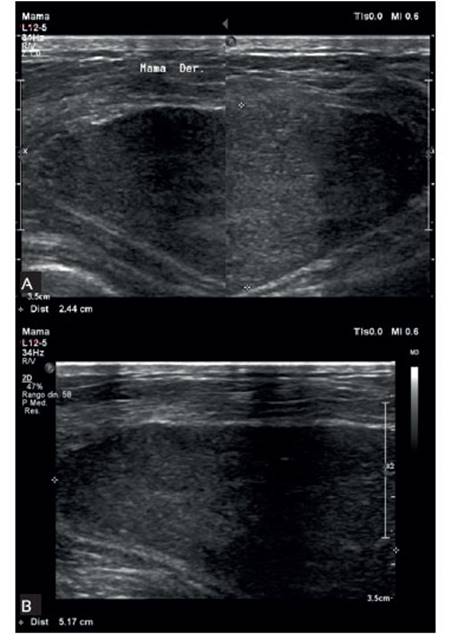

Al examen de ingreso pesaba 53 kg, talla 1,54 m, índice de masa corporal 22,3, colaboradora durante la evaluación. Se observó regular estado general, de nutrición y de hidratación. La mama derecha, en estadio Tanner 4, estaba ocupada por masa única de bordes definidos de 9 x 6 cm, radio 6 hasta radio 12, móvil, no dolorosa, de consistencia dura y que deformaba el pezón y la areola. La mama izquierda, estadio Tanner 4, no mostraba alteraciones. La bioquímica, el examen hematológico y de orina fueron normales. En la ecografía mamaria derecha se observó masa ovalada circunscrita con sombra acústica, de 9 x 6 cm en radio 11 y 12 (Figura 1).

Figura 1 (a, b). en la ecograFía mamaria antes de la cirugía, los hallazgos son variables, Pero en la mayoría se observa una masa sólida, circunscrita, de Forma ovalada o redondeada, como en el caso Presentado.

El diagnóstico diferencial de los tumores de mama es fundamental para el manejo de fibroadenomas, fibroadenomas gigantojuveniles, tumor filodes, linfoma. Entre los exámenes de ayuda, la ecografía11-13,16 de mama en este tipo de tumor es inespecífica, encontrando generalmente una masa sólida, circunscrita, de forma ovalada o redonda. El diagnóstico es anatomopatológico; se describe un parénquima mamario con numerosas hendiduras estromales. Estas hendiduras están revestidas por miofibroblastos15. Los espacios producidos por las hendiduras están vacíos, simulando complejos vasos sanguíneos anastomosados. Las hendiduras están presentes tanto en el estroma interlobulillar como en el estroma intralobulillar.